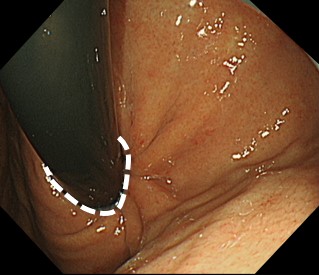

内視鏡で胃と食道のつなぎ目の粘膜を切除して、修復過程で狭くなることを利用して、逆流を防止します。

体の負担が少ない治療で、多くの方で症状改善がみられ、お薬が不要となる方もみえます。